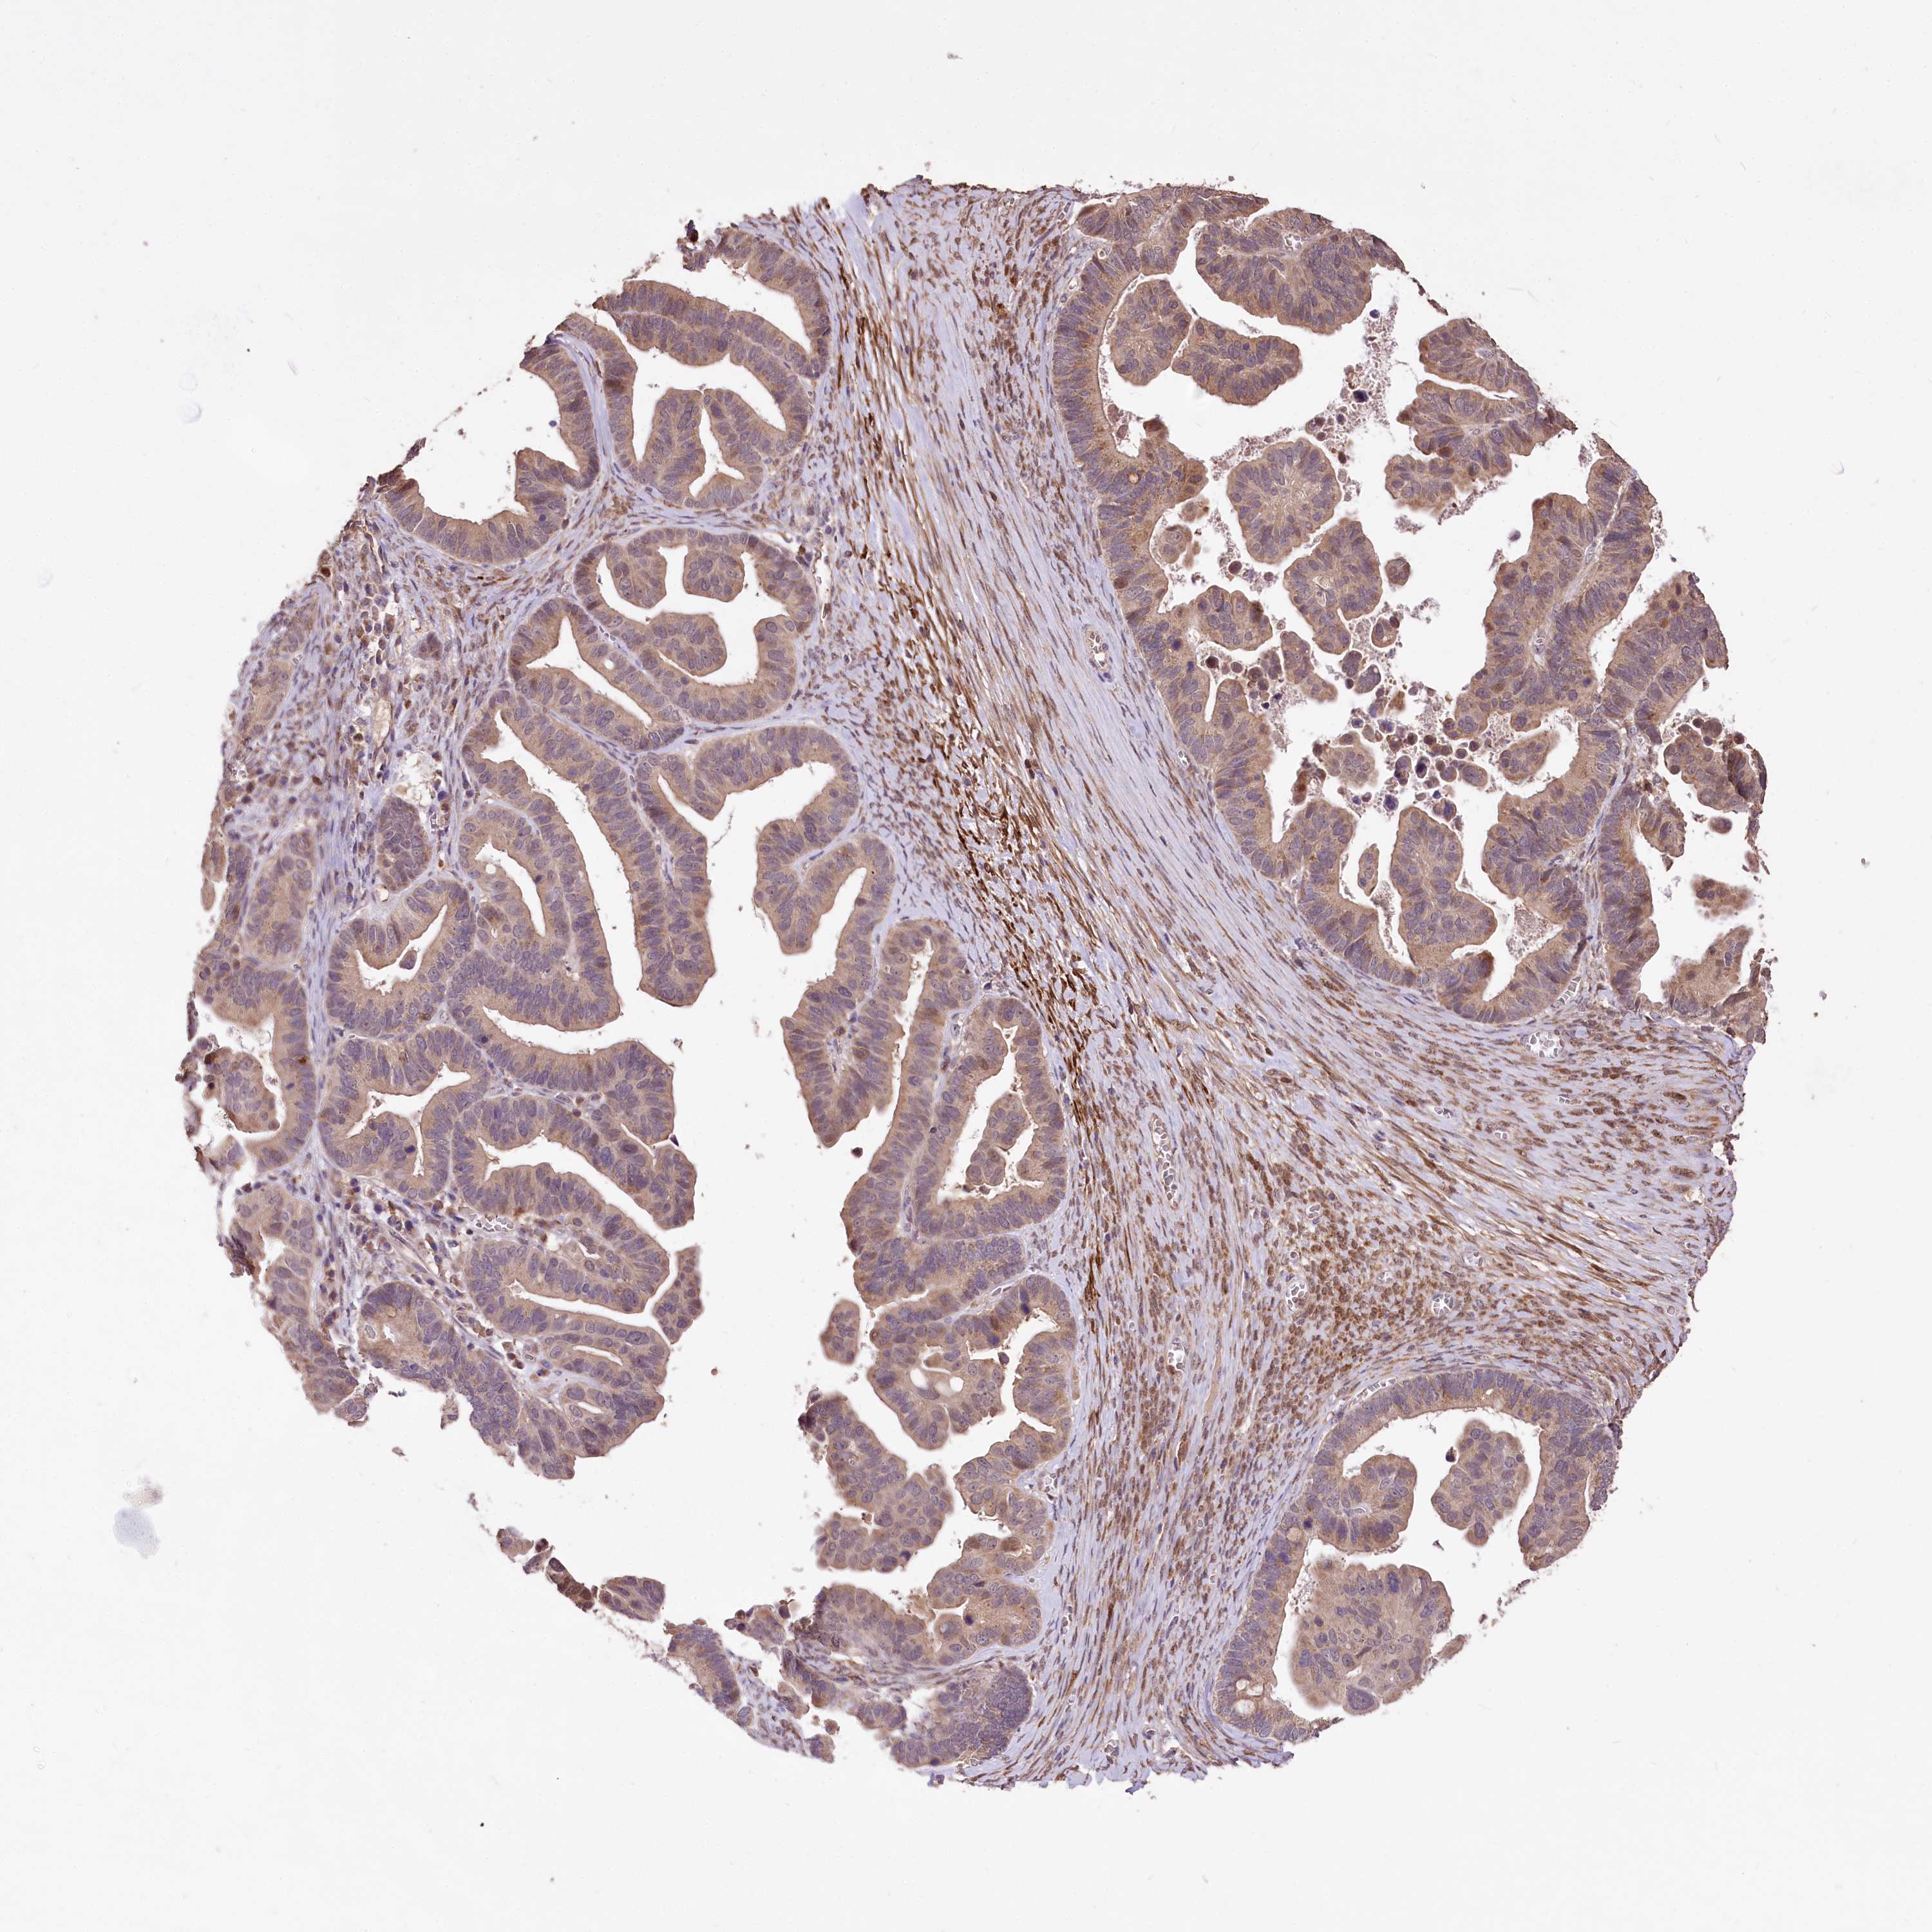

OVARIAN CANCER - Protein expressioni

A mouse-over function shows sample information and annotation data. Click on an image to view it in a full screen mode. Samples can be filtered based on level of antibody staining by selecting one or several of the following categories: high, medium, low and not detected. The assay and annotation is described here.

Note that samples used for immunohistochemistry by the Human Protein Atlas do not correspond to samples in the TCGA dataset.

Antibody stainingi

Antibody staining in the annotated cell types in the current human tissue is reported as not detected, low, medium, or high, based on conventional immunohistochemistry profiling in selected tissues. This score is based on the combination of the staining intensity and fraction of stained cells.

Each image is clickable and will lead to virtual microscopy that enables deeper exploration of all samples and also displays staining intensity scores, fraction scores and subcellular localization as well as patient and tissue information for each sample.

Antibody HPA037811

Antibody HPA037812

Staining

High

Medium

Low

Not detected

Intensity

Strong

Moderate

Weak

Negative

Quantity

>75%

75%-25%

<25%

None

Location

Nuclear

Cytoplasmic/membranous

Cytoplasmic/membranous,nuclear

Cystadenocarcinoma, serous, NOS